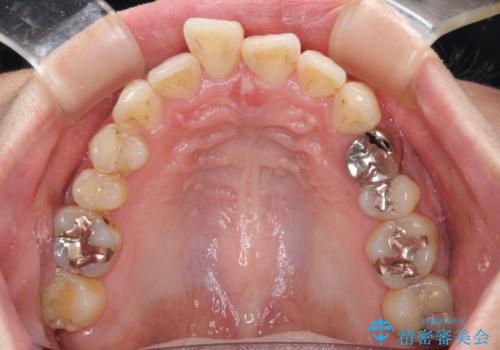

- 出っ歯と口の閉じにくさ、デコボコを気にして来院された患者様です。

口元の突出感を改善するため、上下左右第一小臼歯4本の抜歯を行い、ワイヤー装置による矯正治療を行うこととしました。